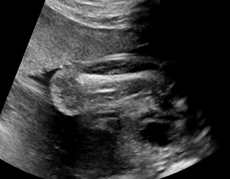

| Abdominal | Brain | Femur | Lips | |

| Device A | ![]() |

![]() |

| Device B | ![]() |

We demonstrate the practical applicability of our method on a challenging medical application, the classification of standardized fetal ultrasound (US) views during prenatal screening. In many countries, US imaging is clinical routine for prenatal health care. The classification of standardized views is important for a consistent, cross-institutional identification of possible abnormalities [47]. Early detection of pathological development can inform following treatment and delivery options [55, 25]. DNNs have shown promising performance to support this task [2]. However, ultrasound images are often hard to interpreted [40]. Anatomical structures have inconsistent appearance [2] and contain different orientations and shapes of anatomical landmarks [1]. Labeled training data is often insufficient as annotating medical images requires significant expertise and is prohibitively expensive in both time and labor. Manifestation of acoustic shadows [17, 44] as shown in Fig. 2(a) as well as different imaging devices as shown in Fig. 2(b) can lead to a domain shift problem for vanilla DNN classifiers. Exploring domain adaptation in fetal US enables DNN classifiers to be effectively utilized on a wider range, which supports identification of abnormalities from varying data sources. This can benefit prenatal healthcare.

We evaluate the proposed method on two fetal US standard plane classification tasks, where the domain shifts are respectively caused by shadow artifacts (Fig. 2(a)) and different image acquisition devices (Fig. 2(b)). For both tasks, images from source and target domains are unpaired and collected independently. We show the key results in the main paper and detailed implementation, network architectures as well as more results in the supplemental Appendix.

IV-D Experiments on cross-device fetal US

The previous experiment on fetal US images is supported by data restricted to one US imaging device. Here, we evaluate MIDNet for a standard plane classification task on data from different imaging devices (different device domains). Device A is “GE Voluson E8” which is the same device in Sec. IV-C, which acquired 2D fetal US images. Device B is “Philips EPIQ V7 G” which acquired another images sampled from about 500 2D US examinations with gestational ages between 20-32 weeks (see Fig. 2 (b)). In this experiment, we use four different anatomical standard plane locations with sufficient images in both domains, including Abdominal, Brain, Femur and Lips, which are selected by an 10-year-experienced sonographer. In this experiment, the source domain is set as device A while the target domain is device B. Training data consists of all four standard planes from the source domain as well as Abdominal and Brain from the target domain. We aim to separate anatomical features (categorical features) and imaging device features (domain features) to obtain generalized anatomical features for achieving high performance of standard plane classification on (Femur and Lips). Here, contains Abdominal, Brain, Femur and Lips from the source domain and contains Abdominal and Brain from the target domain. Hyper-parameters to in Eq. 11 are for the proposed MIDNet model and is additionally for MIDNet+.